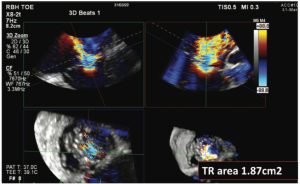

Echocardiography and computed tomography fusion imaging for pre-procedural planning and guidance of transcatheter valvular therapies

By Marcin Fijalkowski Cardiac computed tomography (CT) is increasingly used for the assessment of the [...]